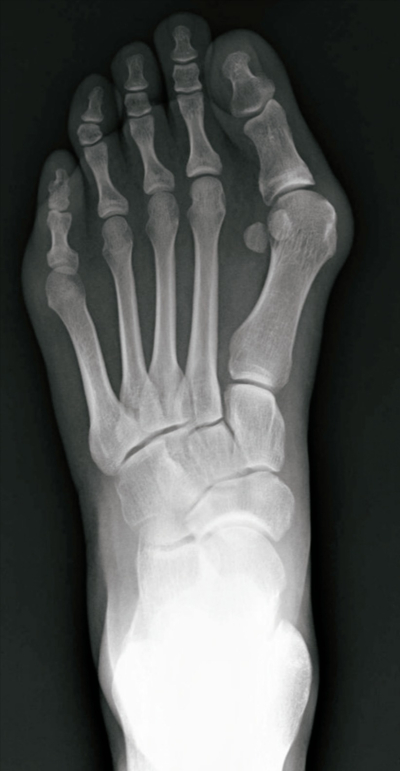

31歳の女性。左母趾痛と同部の変形を主訴に来院した。3年前に誘因なく左母趾痛が出現したがそのままにしていた。最近になり、痛みが増悪し変形も目立ってきたので受診した。左足部エックス線写真を別に示す。

治療として適切でないのはどれか。

a. 靴指導

b. 筋力訓練

c. 骨切り術

d. 装具療法

e. 徒手整復